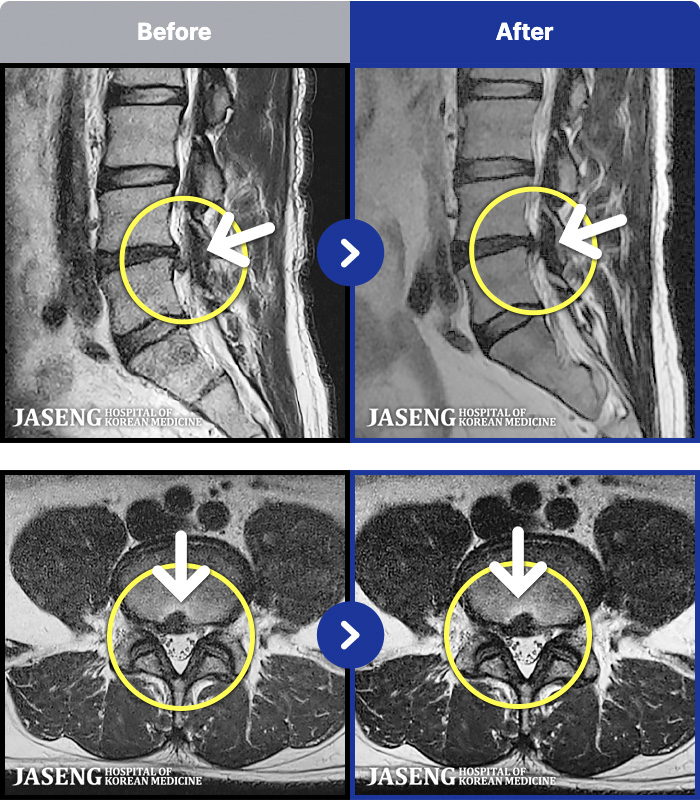

MRI ũ ʸ Ȯϼ.

ȯںп Ǹ ǿ ԿǾ, ο ġ ۿ Ƿ ġḦ Ͻñ ٶϴ.